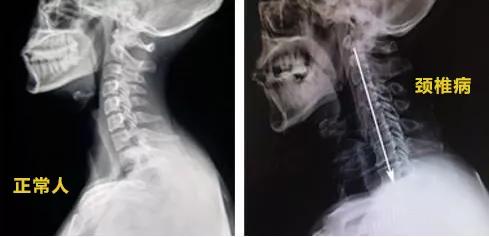

正常人颈椎是带有弯曲的弧度的

而这名9岁男童的颈椎变成了一条直线